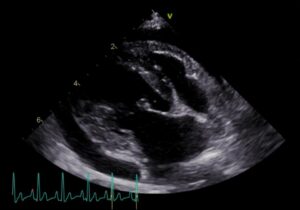

心臓血管肉腫は通常、心タンポナーデに関する症状である活動不耐、呼吸困難、腹水貯留、不整脈等を示します(画像1・2)。

画像2:心嚢水貯留